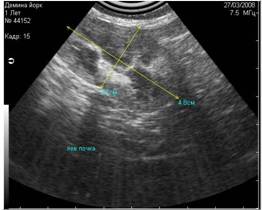

- вызванные недостаточным количеством УЗИ-геля, нанесённого на кожу (Рис.4) ;

Рис 4. Недостаточное количество геля при проведении УЗИ (правая половина снимка). |